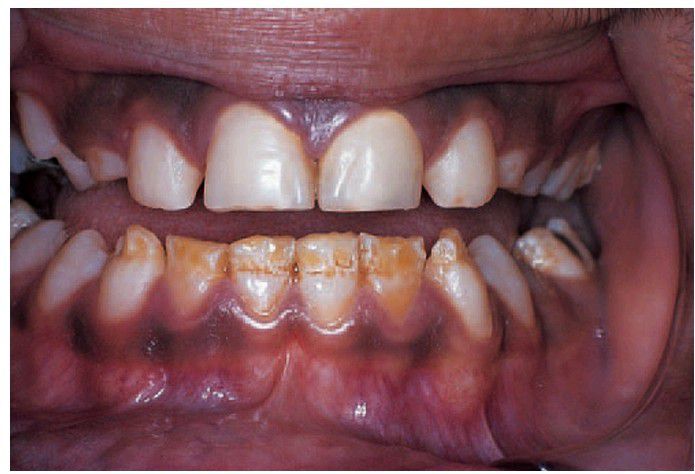

Chronological hypoplasia

Chronological hypoplasia due to metabolic upset. Unlike the hereditary types of amelogenesis imperfecta, defects are linear and thought to correspond to a short period of amelogenesis disturbed by a concurrent severe illness.